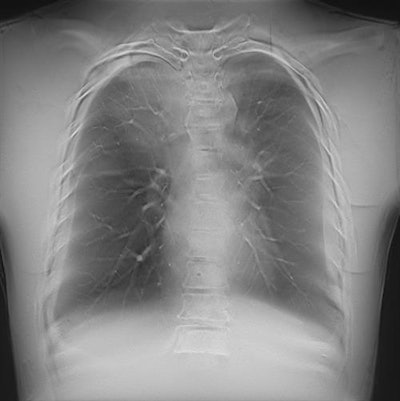

Radiography may be medical imaging's oldest modality, but it's getting a refresh thanks to a wide range of new technologies on display at this week's ECR. The most significant of the techniques is artificial intelligence (AI), but other advances include tomosynthesis and dual-energy imaging.

AI has practically taken over all aspects of radiology since bursting on the scene just a few short years ago. While the technology has applications across all modalities, its use is especially exciting in x-ray, for a variety of reasons.

For one, a number of large, anonymized databases of radiography images have been made available on which AI developers can train and test their algorithms. Second, x-ray is often used as an entry-level modality that's the first to image patients, producing a large volume of images that are frequently difficult to interpret. And radiography is often the only imaging modality available in some locations like developing countries that often have a shortage of radiologists. In these cases, AI could provide an initial interpretation that can triage cases that should be sent on to a human for review.